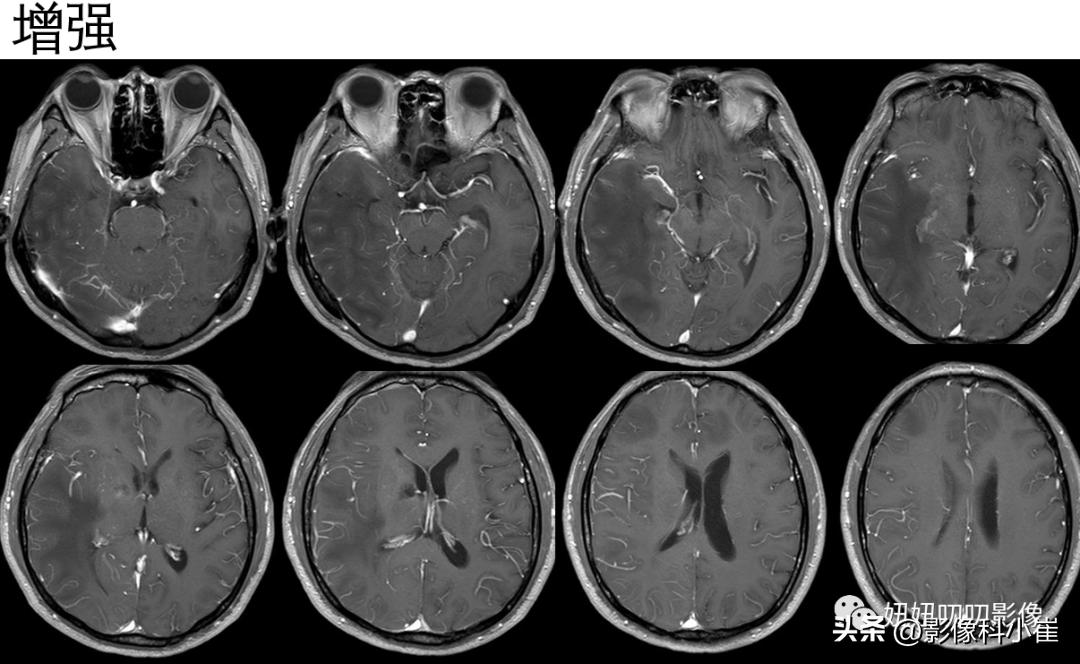

之前有脑梗,再看平扫,但看T2-FLAIR谁知道是肿瘤、脱髓鞘还是血管性病变,结合之前病史,加上MRA血管狭窄,增强没有强化,还是考虑血管性,但是不做SWI真看不出来这么多微出血灶;

做了SWI就能想到脑淀粉样血管病,如果有痴呆和脑出血的征象就更贴合了,可是常规也就来个MRA,T2出血灶明显会有含铁血黄素可见,一般这种病没SWI还真不好看,所以要有个弦啊,痴呆、血管病变、有出血征象,就要来个SWI看看。